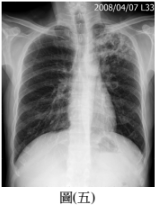

29.50 歲男性,主訴咳嗽有痰,於門診所照的胸部 X 光如圖(五),最可能診斷為何? (A) 肺炎(B) 肺癌(C) 肺結核(D) 塵肺症